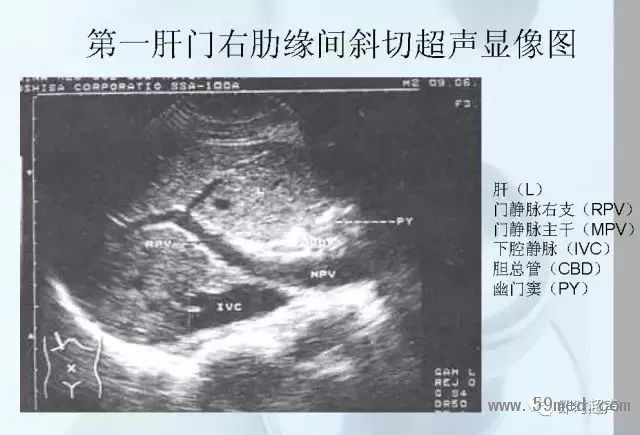

新聞中心 收藏!正常B超解剖圖譜,超實用!